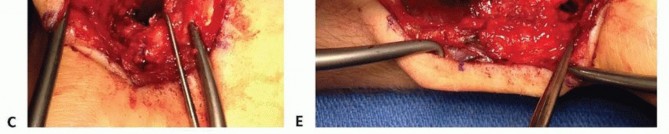

TECH FIG 4 • (continued) C. The scaphoid nonunion site (at tip of Freer elevator) is débrided to remove fibrous tissue. D. The palmar corticocancellous graft (in forceps) is rotated into the nonunion site. E. The graft is press-fit into the nonunion site and secured with internal fixation.

GRAFT PLACEMENT